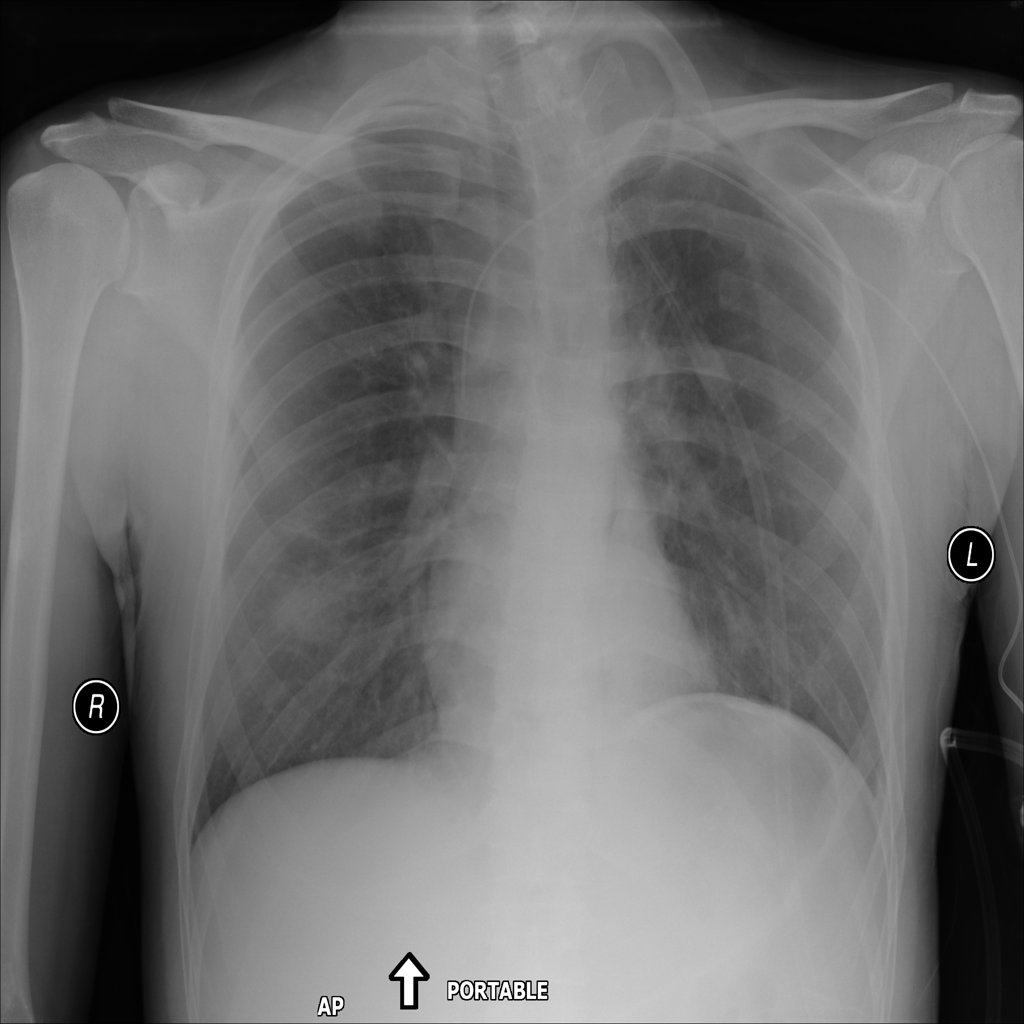

PAT-B733 · IMG-000Consolidation

PAT-B733 · IMG-000

PA